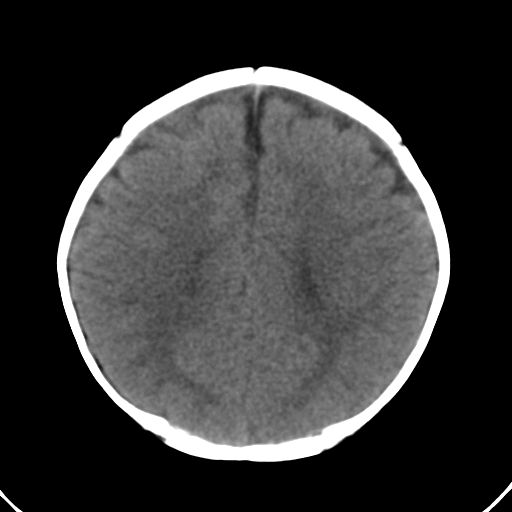

男,10月,足月剖腹产,无缺氧病史,当时评分均正常,学走路时脚后跟不着地!

小孩子片子,看得少,请各位老师看看有问题没?

未见明显异常。

外部性脑积水

考虑外部性脑积水

轻度脑外脑积水表现.